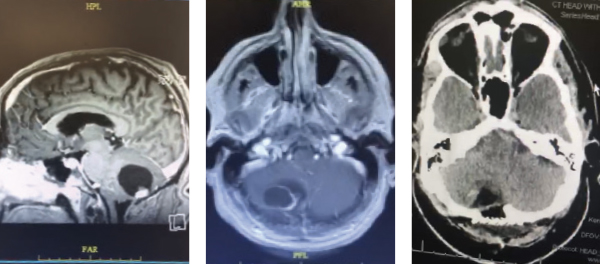

This a 58-year-old man who presented with several months of progressive right occipital headaches. He was experiencing dizziness at times and felt his coordination was off. He felt his gait was also somewhat abnormal. MRI showed a 4 cm right cerebellar cyst with an associated enhancing nodule. He underwent a stereotactic guided right suboccipital craniectomy, performed by Dr. Michael Brisman. Pathology showed hemangioblastoma. Postoperative imaging showed the cystic mass was gone. Postoperatively, the patient felt beer with a complete resolution of his symptoms. Work-up for Von Hippel-Lindau disease (which is associated with hemangioblastomas) was negative.